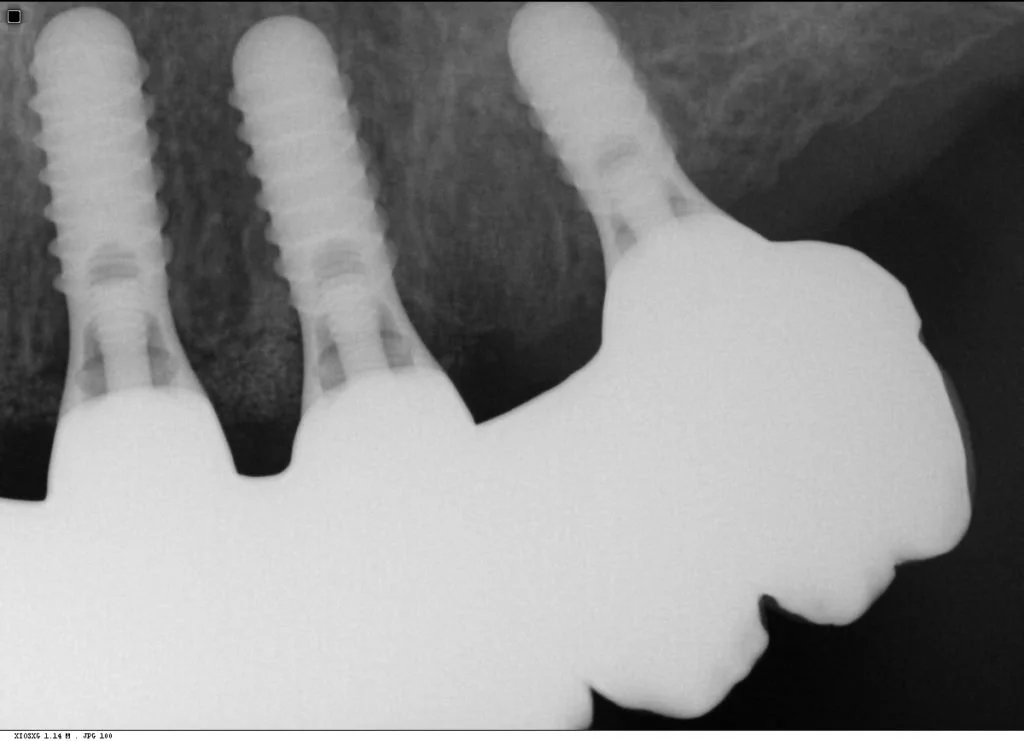

Multiple intra-operative radiographs were taken using depth gauges of gradually increasing diameter to ensure ideal positioning, particularly near vital structures such as the maxillary sinus. Following three months healing, definitive impressions were taken. Radiographs were taken to confirm complete seating of the impression copings prior to splinting of the impression copings and then impression taking.

Records stage: due to the fact that all records were gained by the adjustment and confirmation of the provisional removable complete maxillary denture, records were quite straightforward. The complete denture was copied, flanges were removed, and the resulting guide was then seated over the existing tissue level healing abutments. A PMMA bridge with plastic inserts was constructed digitally in the laboratory and sent for final confirmation prior to construction of the definitive porcelain-fused-to-zirconia bridge. The definitive bridge was inserted and radiographs were taken to confirm full seating and correct emergence profile. Once passivity of fit was confirmed, abutments crews were torque to 35 Ncm, and the access cavities were restored with PTFe tape and composite resin. The occlusion was adjusted to ensure guiding services were smooth, concave and gradually increasing pre-truce in steepness, and smooth shared group function in lateral excursion.